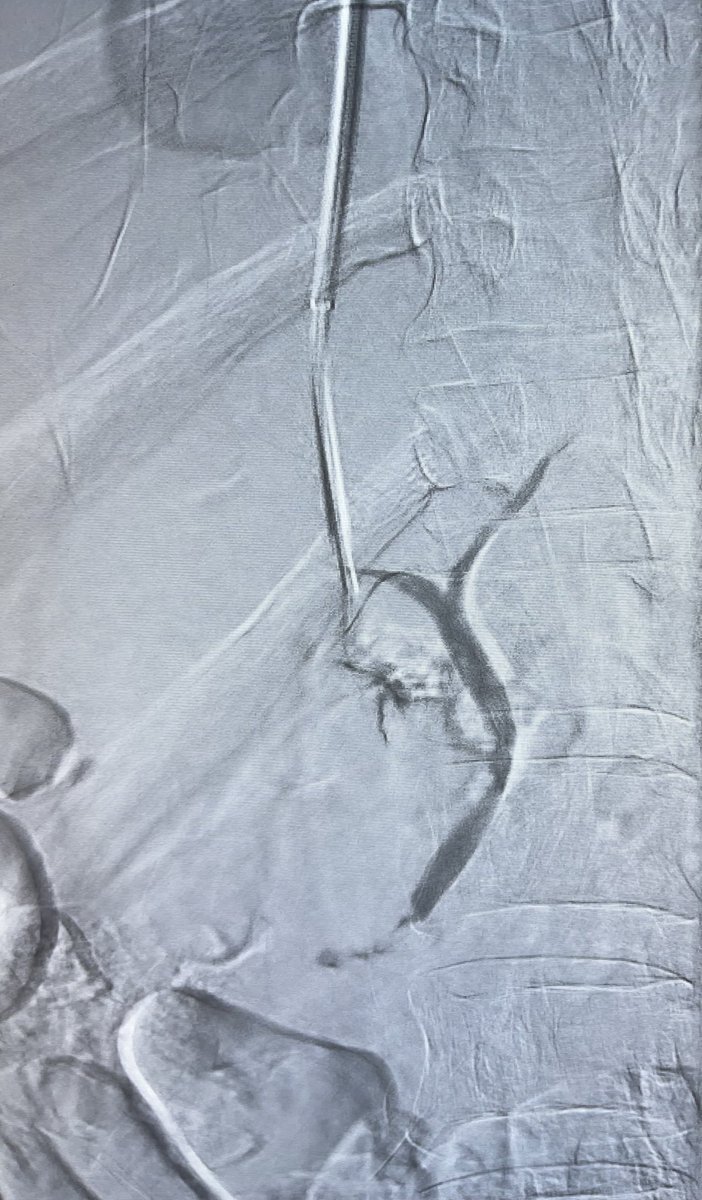

Dr.Amit Sahu is a Neuro & Vascular Interventional Radiologist in Lilavati, Apollo, Wockhardt, SLRaheja, Zen Hospitals in Mumbai offering endovascular treatments

Amit Sahu@MumbaiIR·

What’s happening?